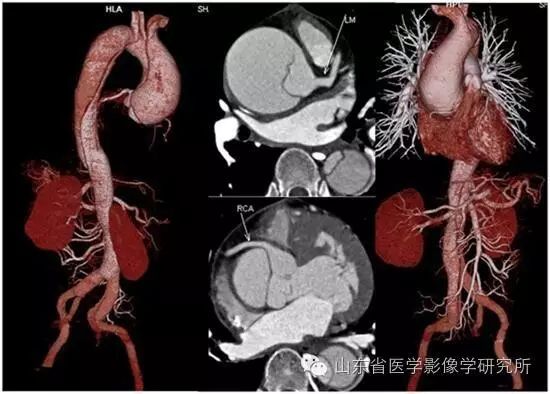

▲主动脉夹层的CTA图像可以清楚地显示受累范围以及破口的位置和大小。

▲儿童肾脏和输尿管畸形的低剂量CTU扫描可以清楚地显示肾脏和尿路反复狭窄和扩张。